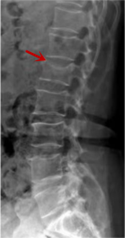

利器一:X线/DR

腰椎X线片作为最基础的影像检查手段,利于X线穿透人体组织后成像,以其快捷、直观、价格低廉的特点,X线检查主要包括腰椎正侧位、双斜位以及过伸过屈位。主要用于观察腰椎骨骼的情况,如椎体是否有骨折、骨质增生程度、生理曲度的变化、椎体移位的情况等。然而,X线检查也有它的局限性,无法判断是骨折的新旧,对于椎体内部结构和周围肌肉韧带组织(如脊髓神经、椎间盘、韧带等)的显示不佳,另外X线作为有辐射检查,孕妇及婴幼儿谨慎选择。

箭头提示腰1椎骨折

箭头提示腰3椎体滑脱